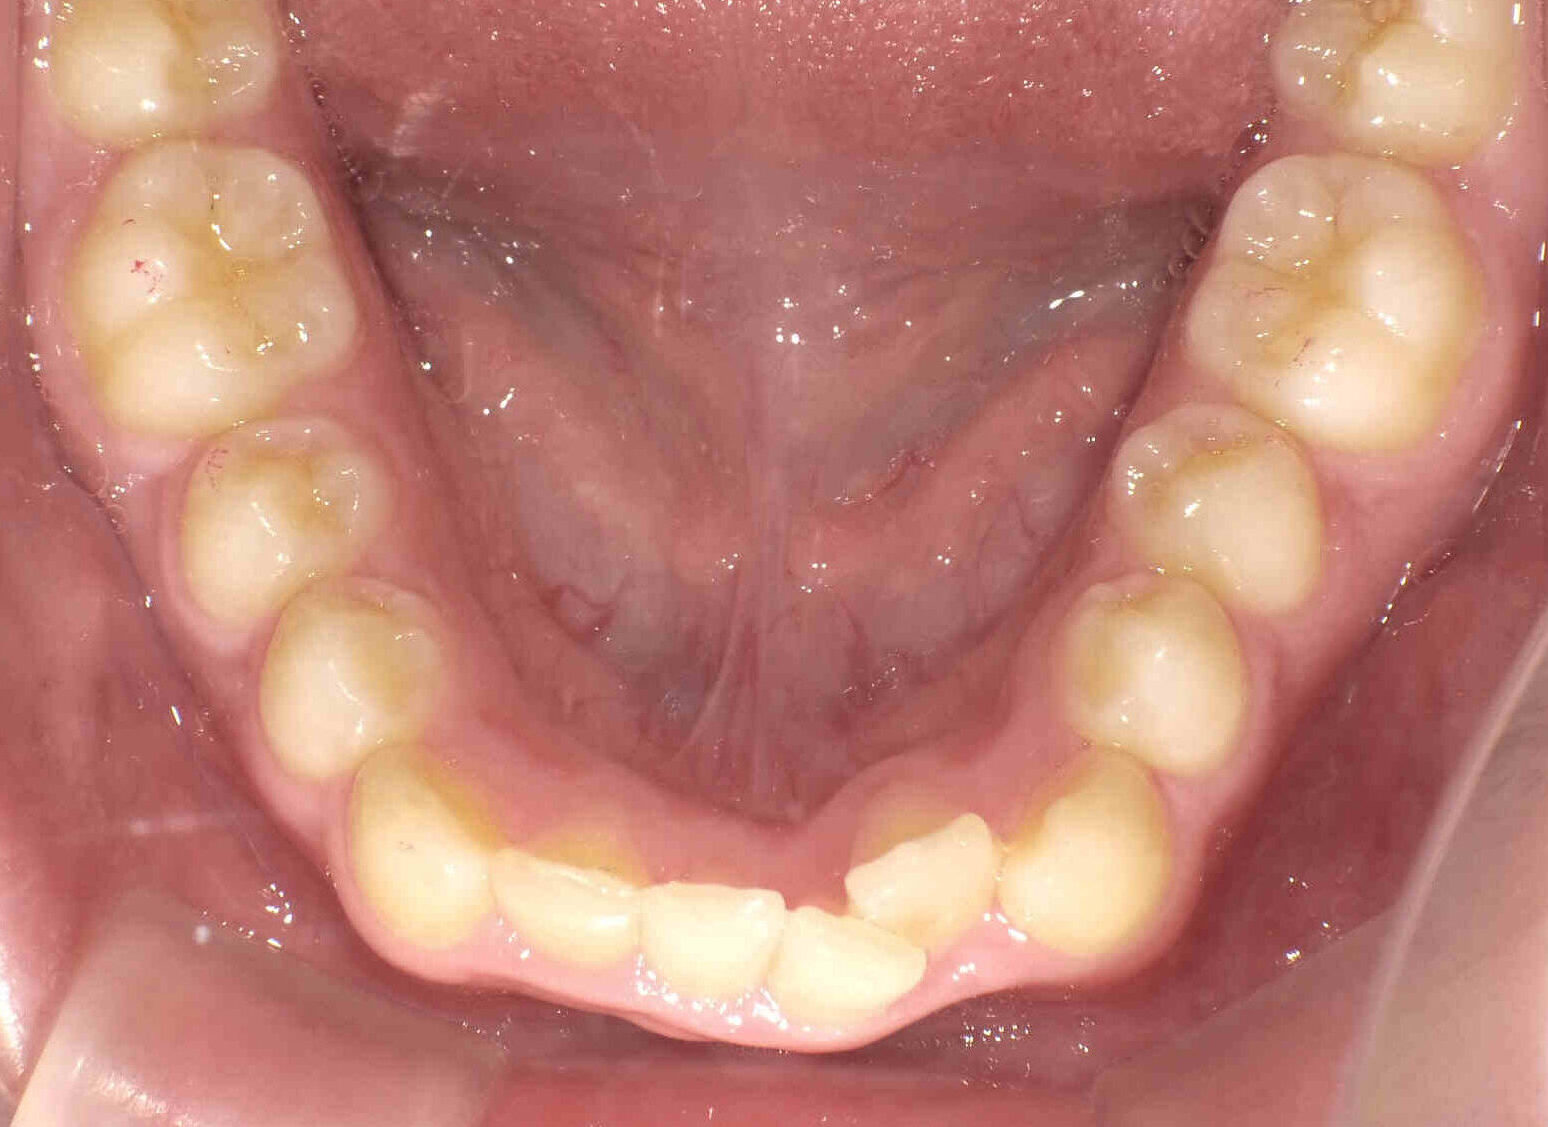

【小児矯正】過蓋咬合と出っ歯

12歳6ヶ月〜スタートです。

やや出っ歯傾向で、噛み合わせが深く

歯並びがデコボコな鋏上咬合(はさみじょうこうごう)という状況でした。

上下の歯がすれ違っている状態で、一部の歯に過度の負担がかかってしまいます。